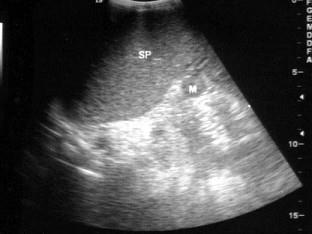

问题 患者男37岁,乙肝患者肝硬化。B超检查如图所示,脾门处包块,根据超声声像图,诊断为

选项 A.脾门淋巴结肿大???(???) B.副脾 C.脾门占位 D.腹腔占位 E.肾上腺肿瘤

答案 B